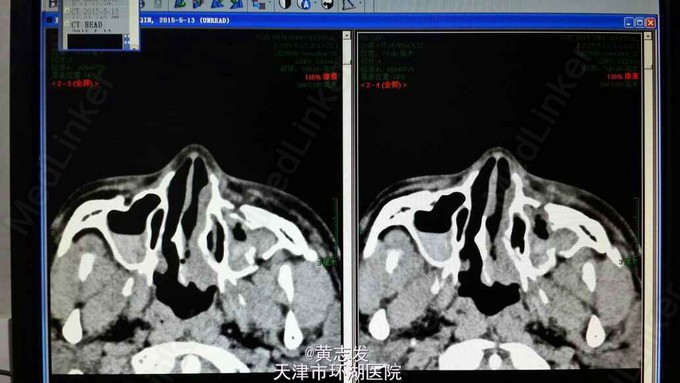

多发颅骨骨折合并视神经损伤

神清可语,右眼自动睁眼,左眼睑下垂,对答切题,四肢遵嘱活动,肌力4+级,右眼直接对光反射(+),间接对光反射(–),左眼直接以及间接对光反射(–);右眼活动自如,视力粗测正常,左眼外展位,无光感。

急性闭合性轻型颅脑损伤,GCS15分:1,额骨,蝶骨,筛骨,上颌骨骨折;2,左侧视神经以及动眼神经损伤;3,双额挫伤